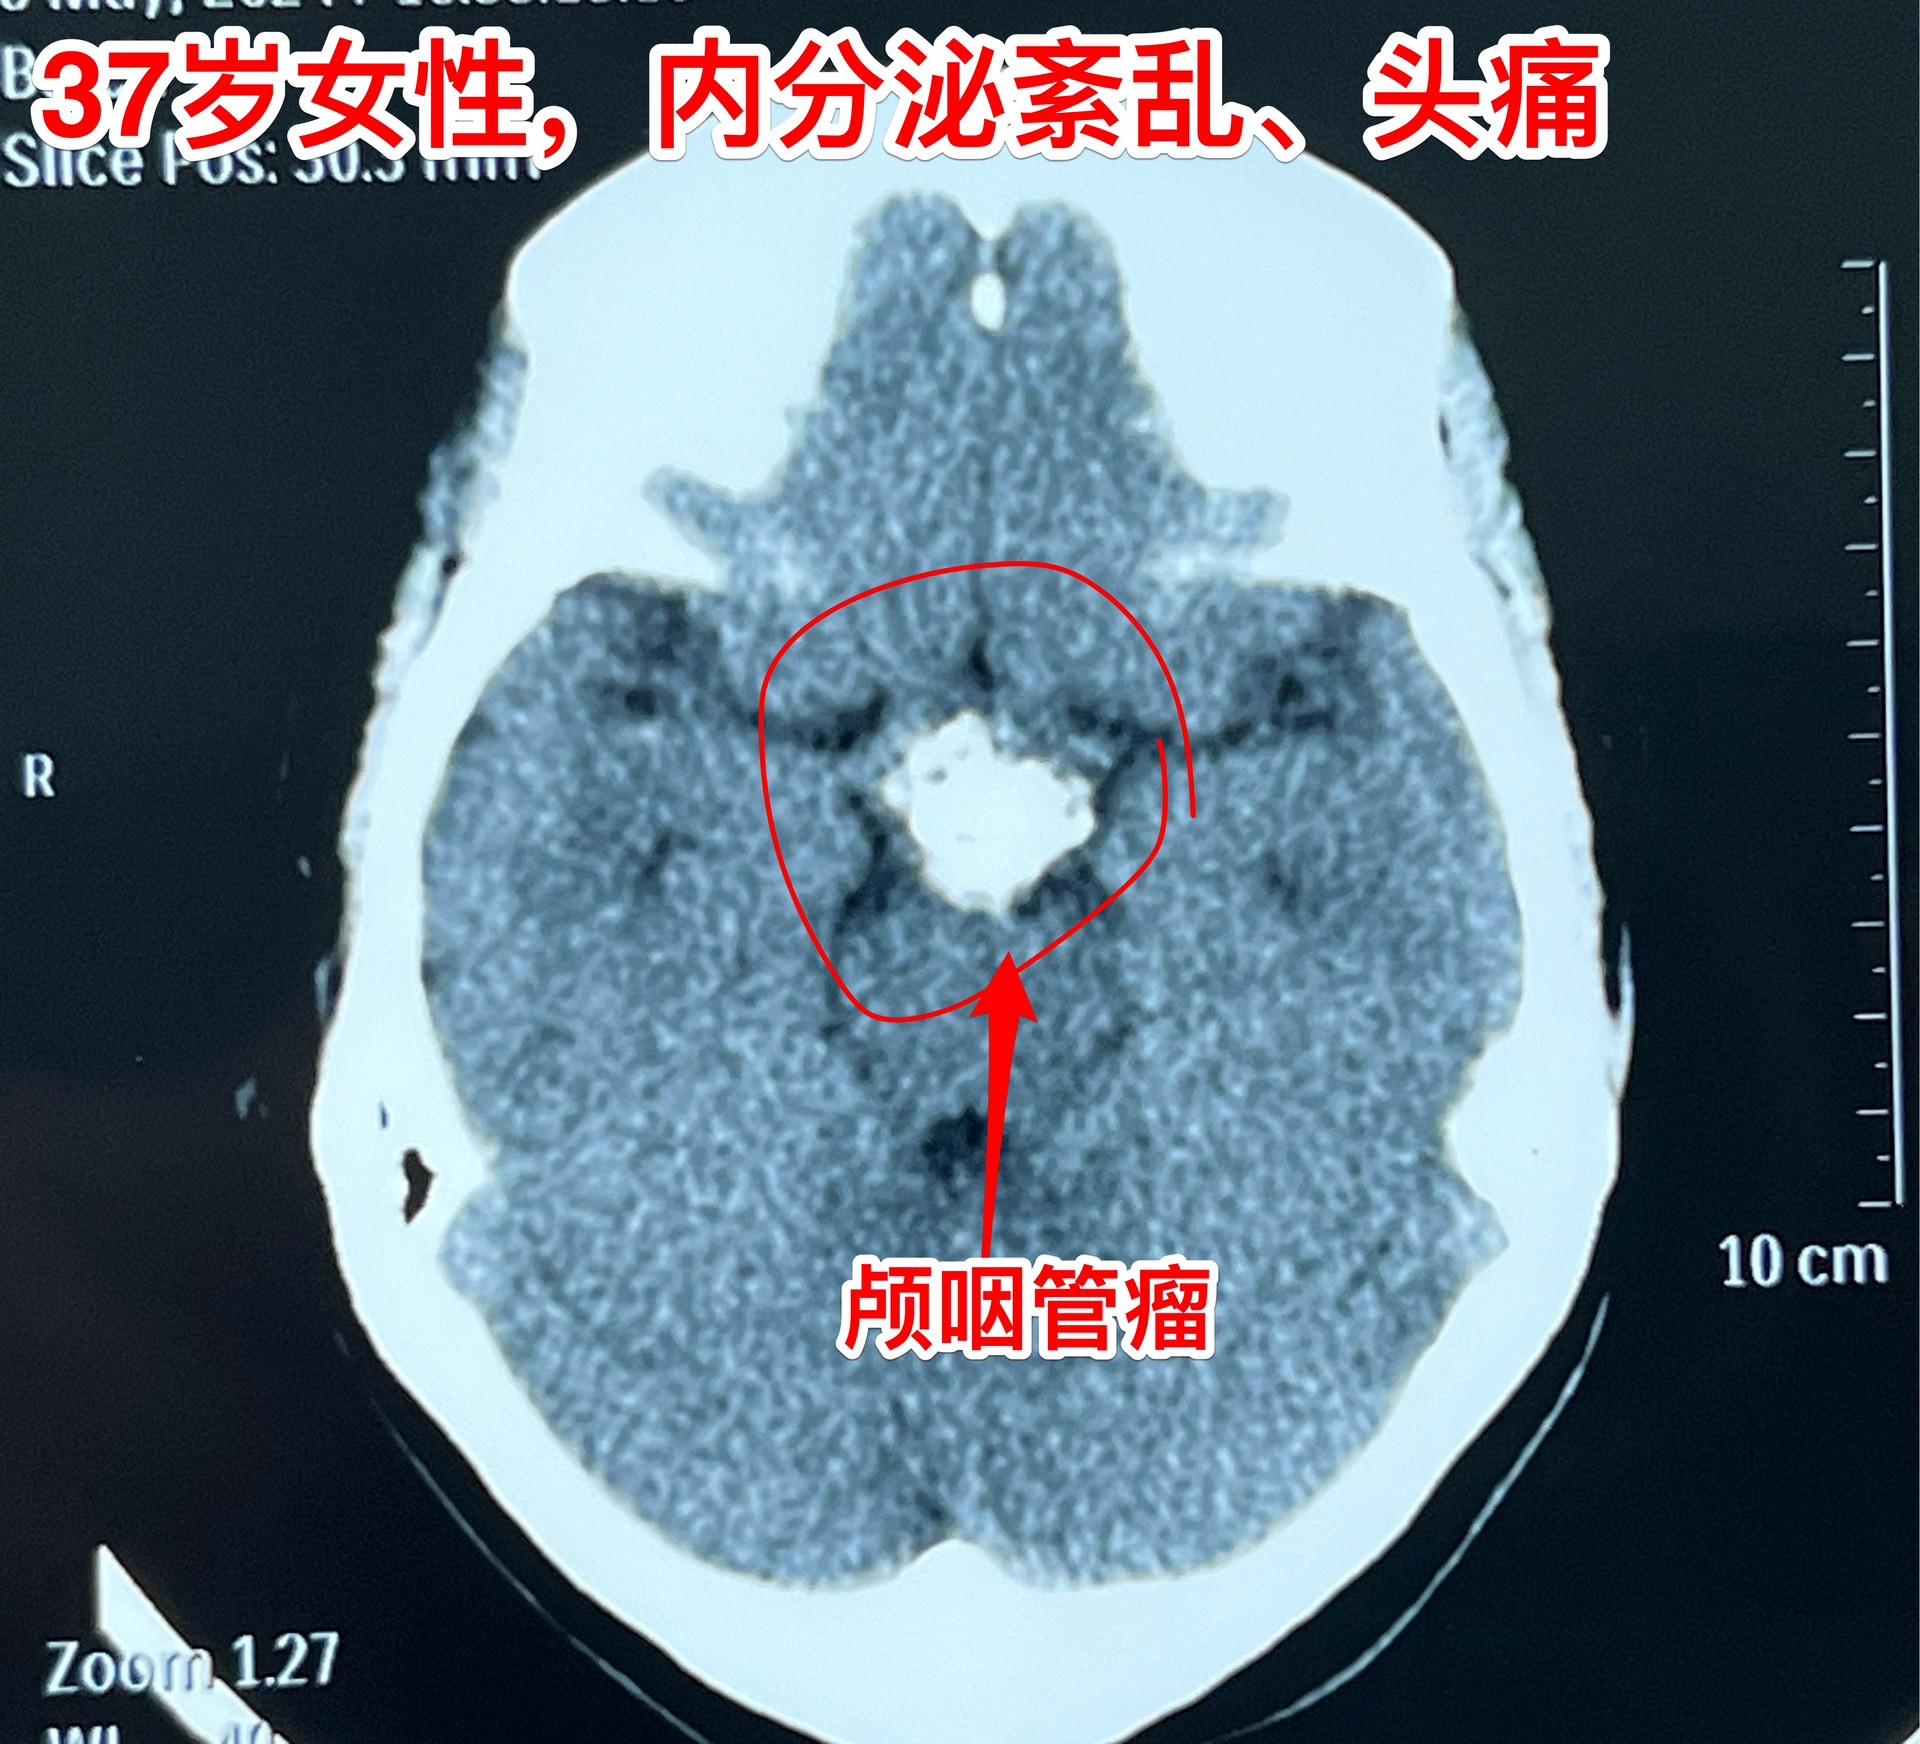

5月16日两个颅咽管瘤手术。五一假期后开展的手术都是颅咽管瘤切除手术。经常一天作两个颅咽管瘤手术!这样的劳动强度有点大! 5.16一天两个颅咽管瘤手术,肿瘤有相似的特征,两个都有大块的钙化斑;都是从垂体柄侵入垂体中;手术方式也相似-经额底纵裂入路。 手术后两个病人都顺利从ICU转移到普通病房。

5月16日两个颅咽管瘤手术。五一假期后开展的手术都是颅咽管瘤切除手术。经常一天作两个颅咽管瘤手术!这样的劳动强度有点大! 5.16一天两个颅咽管瘤手术,肿瘤有相似的特征,两个都有大块的钙化斑;都是从垂体柄侵入垂体中;手术方式也相似-经额底纵裂入路。 手术后两个病人都顺利从ICU转移到普通病房。颅咽管瘤